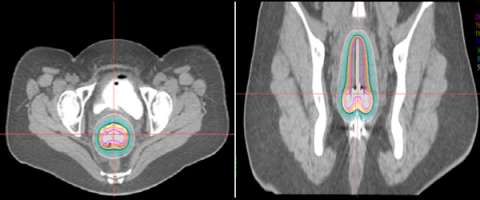

Below is an actual example of the CAPRI applicator (a 13 channel applicator) and the distribution of radiation dose that was delivered around the vaginal apex (right image axial and left image sagittal). Below to the right is a 3D depiction of the anatomy and distribution of the radiation dose (bladder in yellow, rectum in brown, applicator in purple, radiation dose in red):